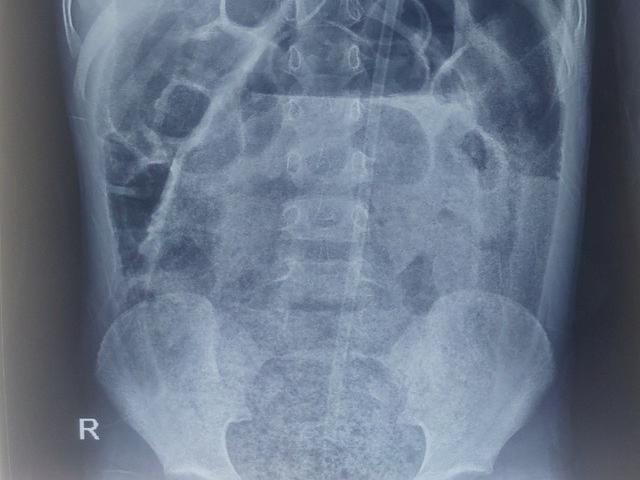

Trời lạnh, ngoài việc chú ý đến các bệnh lây nhiễm qua đường hô hấp, mọi người cần phải cẩn trọng với các bệnh về đường ruột. Ngô Trường Đằng, bác sĩ cấp cứu khoa Nhi tại Trung Quốc cho biết, gần đây đã tiếp nhận một trường hợp bé trai 9 tuổi đau bụng tới mức không thể đi lại và được bố mẹ đưa đến bệnh viện cấp cứu. Sau khi chụp X-quang, bác sĩ phát hiện ruột của bé trai này chứa đầy phân. Cũng trong ngày hôm đó, bác sĩ Ngô tiếp nhận 3 trường hợp tương tự.

Ruột cậu bé chứa đầy phân.